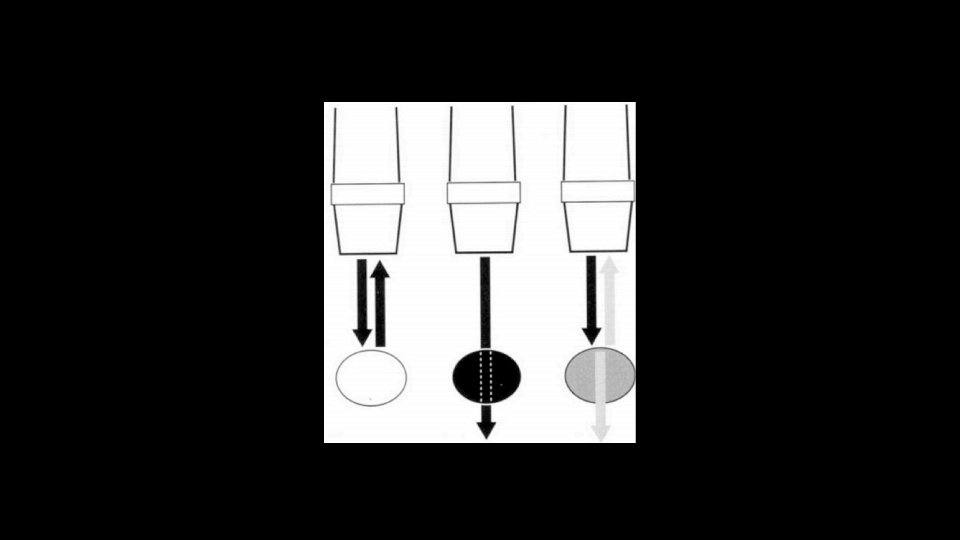

Pleural Line • Look for sliding sign • Still above the pleura and movement below • Comet tails • M mode – Sands on the beach